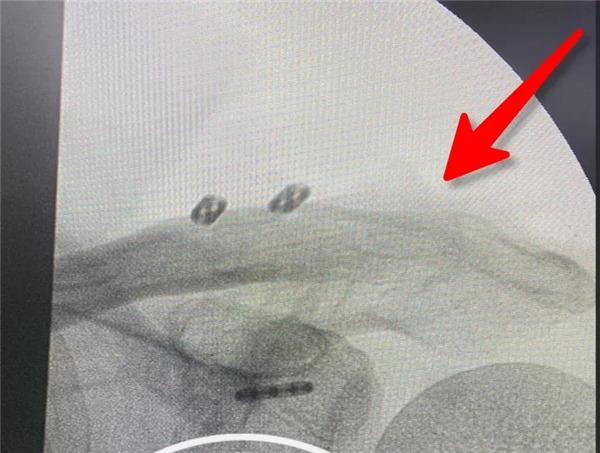

經(jīng)患者與家屬同意后,羅軍主任手術(shù)團(tuán)隊成功為患者實(shí)施了左肩鎖關(guān)節(jié)復(fù)位Y型Endobutton固定系統(tǒng)固定術(shù)。手術(shù)只用50分鐘時間。術(shù)后X片復(fù)查顯示肩鎖關(guān)節(jié)脫位完全復(fù)位,術(shù)后第二天楊女士在康復(fù)醫(yī)師指導(dǎo)下開始進(jìn)行左肩關(guān)節(jié)功能鍛煉,楊女士左肩部疼痛明顯減輕,左肩關(guān)節(jié)可抬起、前舉,功能較術(shù)前明顯改善,楊女士大約再經(jīng)過3-4周康復(fù)訓(xùn)練左肩關(guān)節(jié)功能可恢復(fù)正常。

術(shù)后拍片